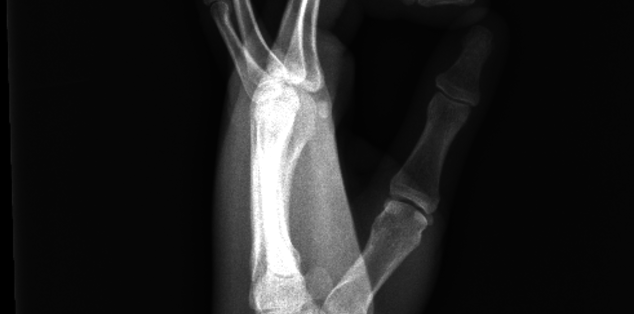

Emily, Fractured 5th Metacarpal

On March 19 I was about 15 miles in on the 50k race known as HAT. There was a large rock on the trail and I utilized my left hand to attempt to break my fall. I got back up and kept running. The next day I had severe pain and increased swelling. I went to morning breakfast with my running club and the foot doctor told me to get it x-rayed. I went to a prompt care in DE and x-ray revealed a spiral fracture of the 5th metacarpal on my left hand. I was devastated and in shock. I'm an ultra runner and for me being told by that doctor that I couldn't run my upcoming race was like being told you can't breathe.